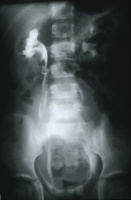

Die abdominale Sonographie bzw. die Computertomographie haben die Ausscheidungsurographie als die bildgebende Untersuchungstechnik bei Patienten mit Oberbauchtumor, z.B. Wilmstumor, verdrängt. Einige Ausscheidungsurographien von Kindern mit Wilmstumoren aus unserer Sammlung aus den 70er Jahren des vergangenen Jahrhunderts sind aus didaktischen Gründen hier wiedergegeben. Die Bilder zeigen instruktiv die Größe und Verdrängung durch den Tumor (

4 Abbildungen HG1).